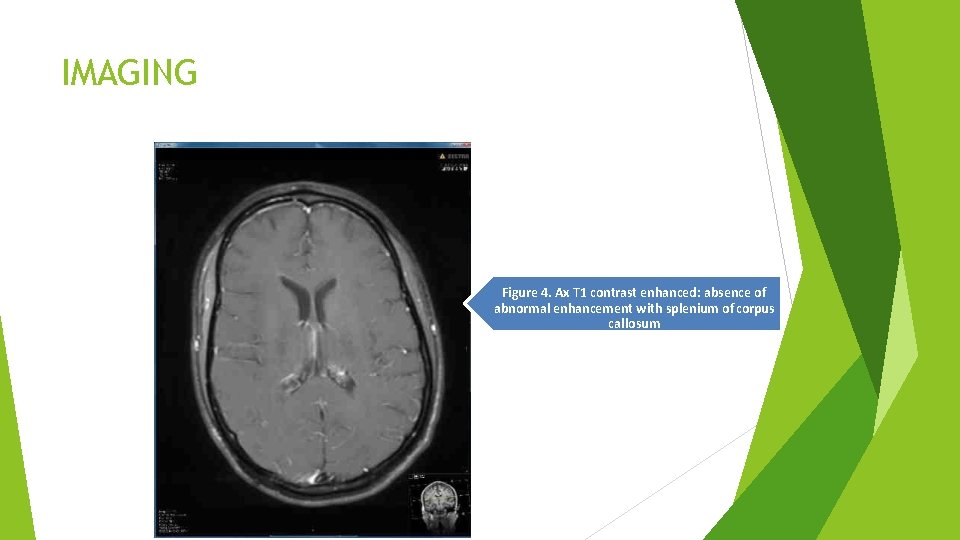

IMAGING Figure 4. Ax T 1 contrast enhanced: absence of abnormal enhancement with splenium of corpus callosum

Imaging � � � CT brain w/o contrast: No acute ischemic stroke or hemorrhage CT angio: Not diagnostic due motion artifact MRA head: No gross aneurysm or vessel wall irregularity MRA neck: No stenosis MRI W/WO contrast: showed diffusion abnormality with associated restriction involving: splenium symmetrically � subcortical white matter of the centrum semiovale, right greater than the left side with no associated abnormal enhancement � no mass effect �At this point, the differential diagnosis was MBD versus diffuse encephalitis/encephalopathy with reversible splenial lesions versus osmotic demyelinating disease.

Imaging Contd. � Fluid attenuated inversion recovery (FLAIR) showed three lesions: � 1. Right centrum semiovale dominant lesion, 2. Left centrum semiovale small lesion and 3. Large lesion in splenium of corpus callosum. � DTI Tractography: Showed significantly diminished commissural fibers extending to the right central semiovale lesion. Near absent or significantly diminished commissural fibers extending through the splenium of corpus callosum indicating demyelination. � Fractional Anisotropy (FA) on DTI. Absence of transverse (red-color coded fibers in splenium of corpus callosum).